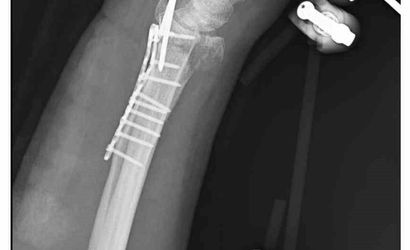

Ankara'nın Mamak ilçesinde, 29 Aralık günü meydana gelen olayda 35 yaşındaki Yasin Arslantaş, yaşadığı apartmanın önünde karşılaştığı sahipsiz köpeklerden kaçmaya çalışırken ayağının kayması sonucu düştü ve el bileği kırıldı. Olay sonrası ambulansla hastaneye kaldırılan Arslantaş'ın bilek kemiğine 11 adet platin yerleştirildi.

Arslantaş, olay anını şöyle anlattı: 'Sabah apartmandan çıkarken arkamdan 9 köpeğin geldiğini gördüm. Saldırganlardı. Kaçmaya çalışırken düştüm.' Yaralanma sonucu bileğinde 15 dikiş olduğunu, geçirdiği ameliyatın 3 saat sürdüğünü ve kolunda kalıcı his ile hareket kaybı olabileceğinin kendisine bildirildiğini söyledi.